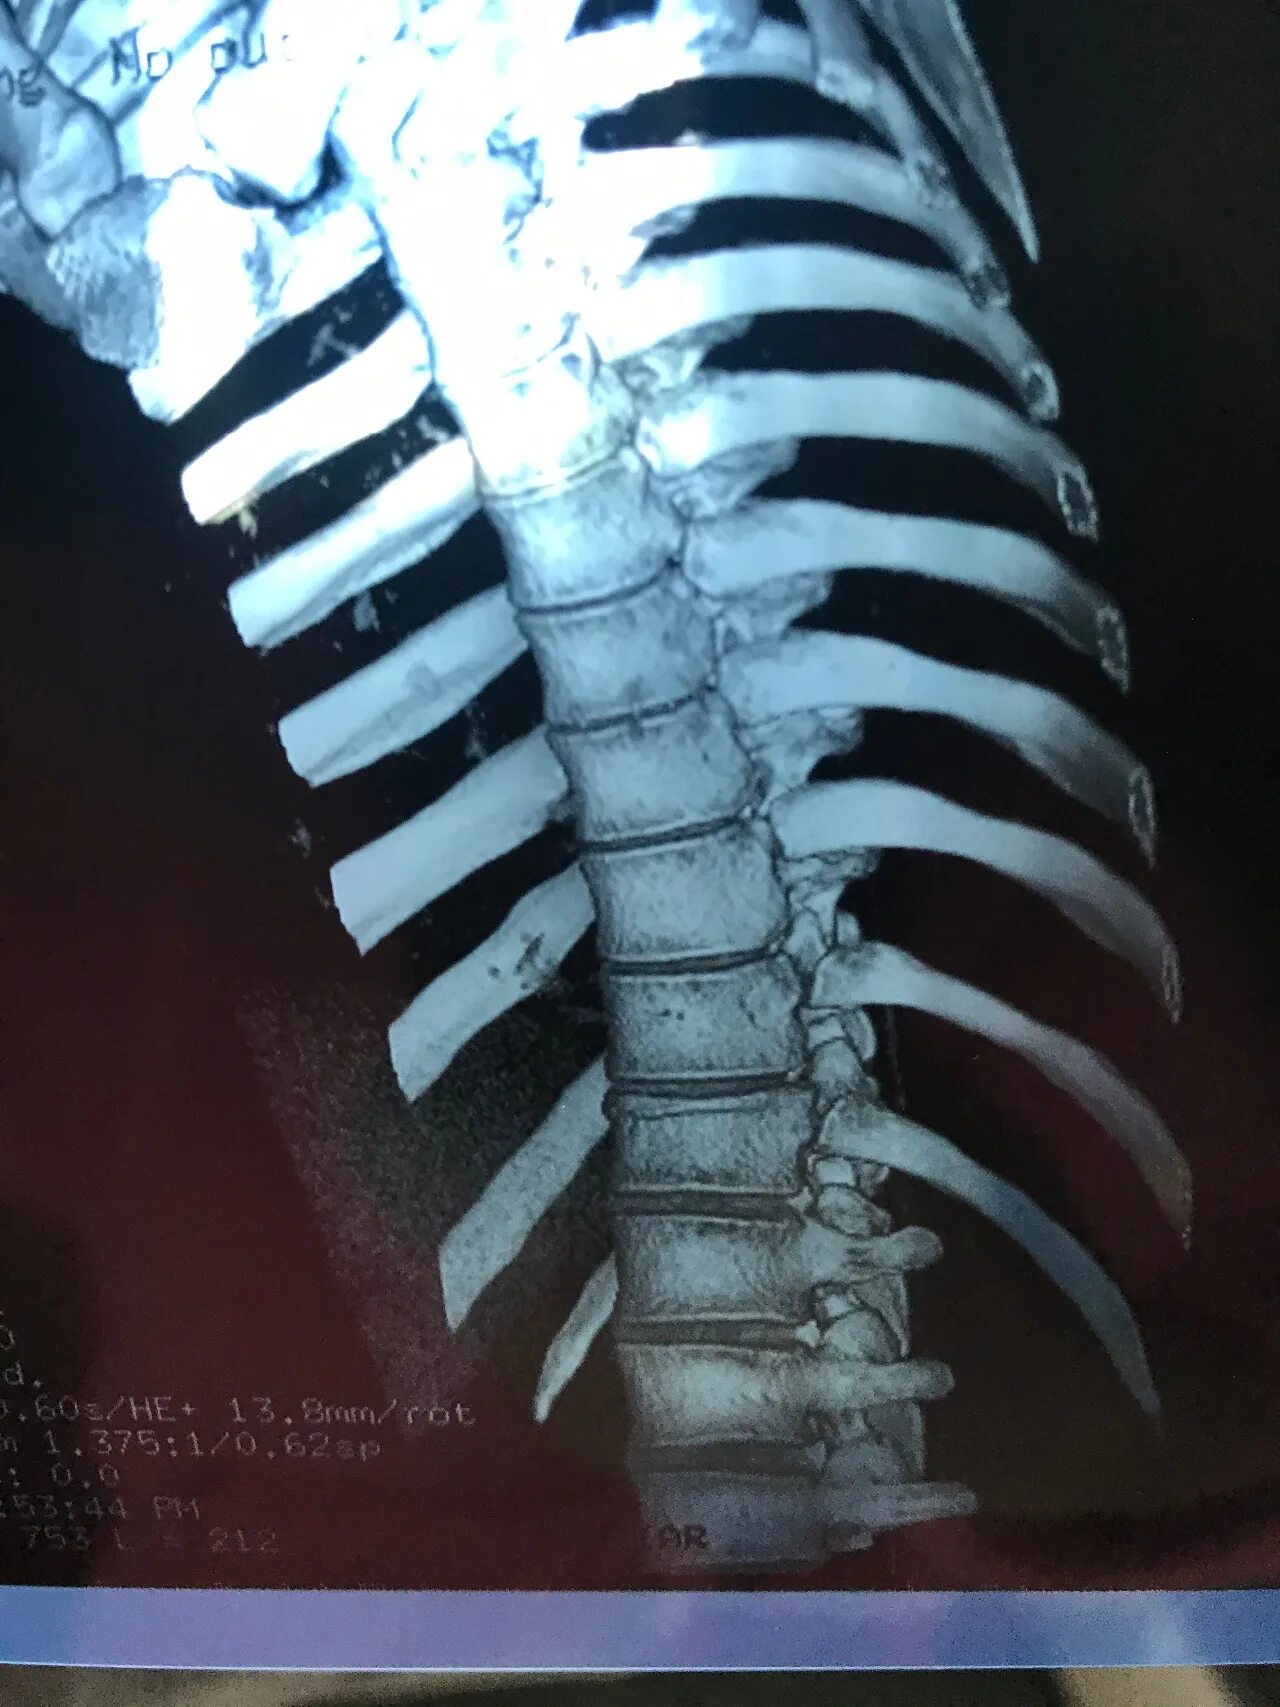

Перелом позвонка инвалидность